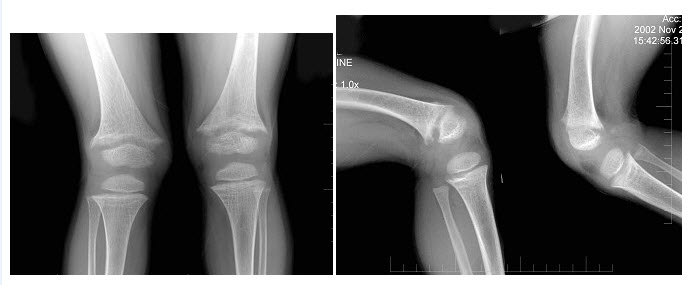

251、单项选择题

女,48岁,常感中上腹不适,无返酸、嗳气及黑便史,结合图像,最可能的诊断为()

A.正常肠圈

B.十二指肠炎

C.球部溃疡

D.降段憩室

E.水平段憩室